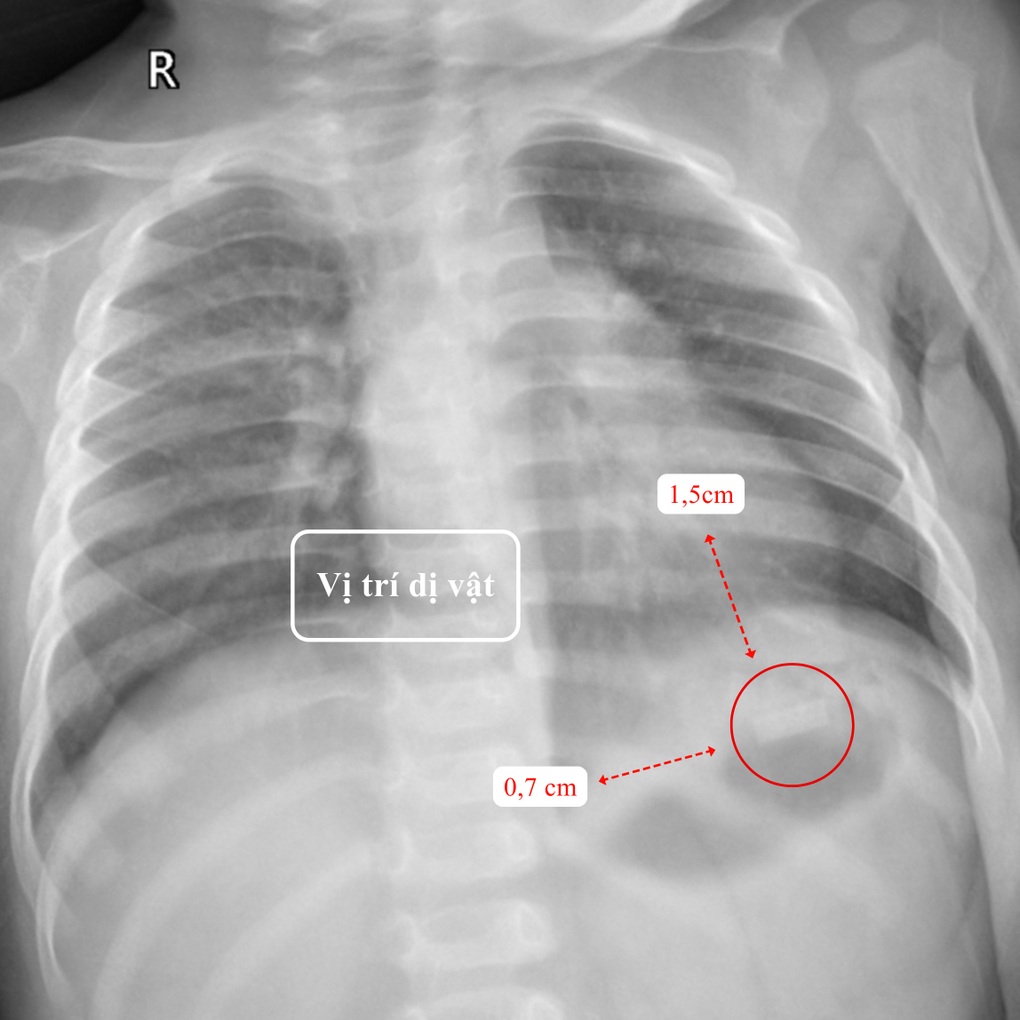

Tại Khoa Nhi – BVĐK Hồng Ngọc – Phúc Trường Minh, kết quả thăm khám lâm sàng và cận lâm sàng cho thấy một dị vật kim loại hình chữ nhật kích thước 1,5×0,7cm, có góc nhọn, mỏng và sắc như lưỡi dao nằm tại vùng hạ sườn trái, vị trí bóng hơi dạ dày của bé T. Ngoài ra, do nuốt phải một phần thuốc lá, trẻ có biểu hiện say thuốc với triệu chứng mệt mỏi, môi tái.

Vị trí dị vật trên phim chụp X-quang (Ảnh: BVCC).